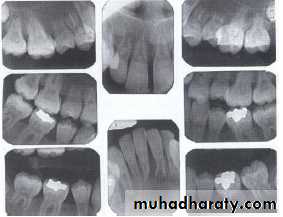

Supernumerary teeth:

Paramolar blocking the eruption of 3rd molar.

MesiodensDistomolars(4th molar)

Mesiodens

Distodens or distomolarParamolar

Supplemental